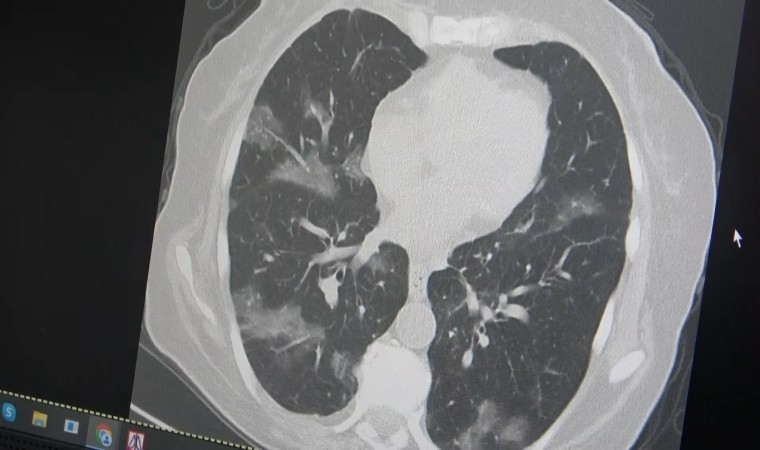

Kanser hastası bir kişinin akciğerleri üzerinde örnek veren Özkaya, “60 yaşının üstünde olduğu ve kemoterapi aldığı için virüsün kolayca ciğerlere indiğini görüyoruz. Bu yaza damgasını vuracak yeni virüsün bu olduğunu düşünüyoruz” ifadelerini kullandı.